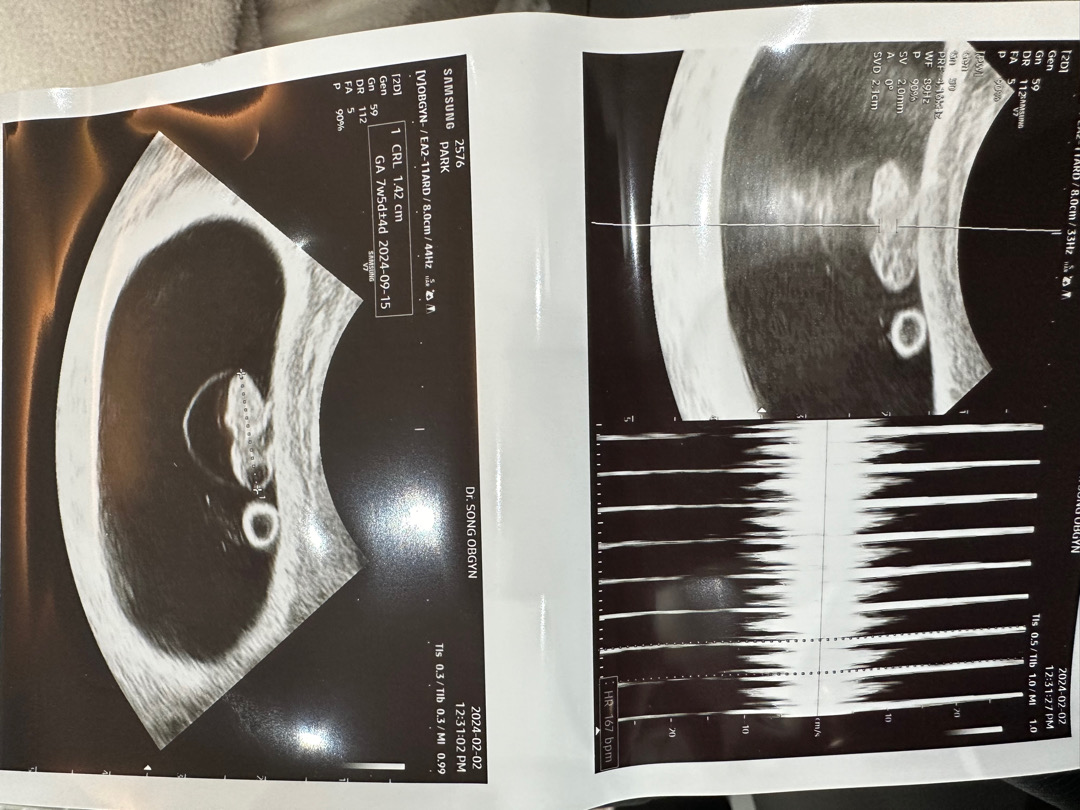

우리 이브 심장소리듣고왔어요(7주5일)

심장소리들으면 성별 알수있다는데 많이 궁금하네요^^